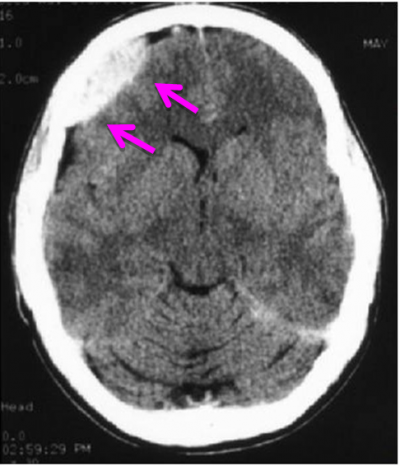

פצוע עם חשד להמטומה אפידורלית חייב לעבור בדיקת טומוגרפיה ממוחשבת של המוח לאישור האבחנה (תצלום 1.16). האבחנה של המטומה אפידורלית מחייבת טיפול נוירו-כירורגי דחוף הכולל ביצוע חורים בגולגולת וניקוז ההמטומה. ניקוז ההמטומה יפחית את הלחץ התוך-גולגולתי וישפר את מצב החולה.